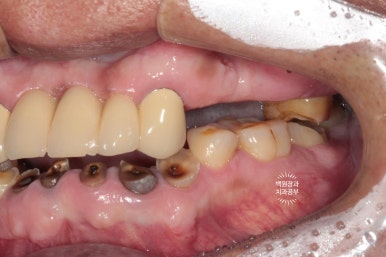

위 어금니와 아래 앞니가 없는 상태입니다.

보시면 아주 최소한의 치아만 닿고 있는게 보이시죠?

성인 남성의 턱 힘을 견뎌내기에 무리가 있어요. 그래서 치아가 자꾸 깨져나가게 되지요.

여담입니다만, 왼쪽 사진을 보시면 임플란트 상부가 구강내로 노출된 것을 보실 수 있을거에요.

흡연자의 경우 담배 연기가 혈관이 수축하게 하는 역할을 하기 때문에 치유가 상당히 더뎌집니다.

그래서 수술 부위가 불완전하게 아물게 되고, 원치 않게 임플란트의 일부가 노출되게 되어요.

또한 골재생도 불량해지고 이후 임플란트의 예후 또한 좋지 않습니다.

그래서 이러한 치료를 받으시기 전에 금연이 선행되어야 하는 것이 원칙입니다.!!

건강한 구강관리를 위해 금연..... 꼭 해주셔야해요 !!!!!

적어도 연초는 금해주세요. 전자담배로 교체라도 꼬옥 !!!!!!